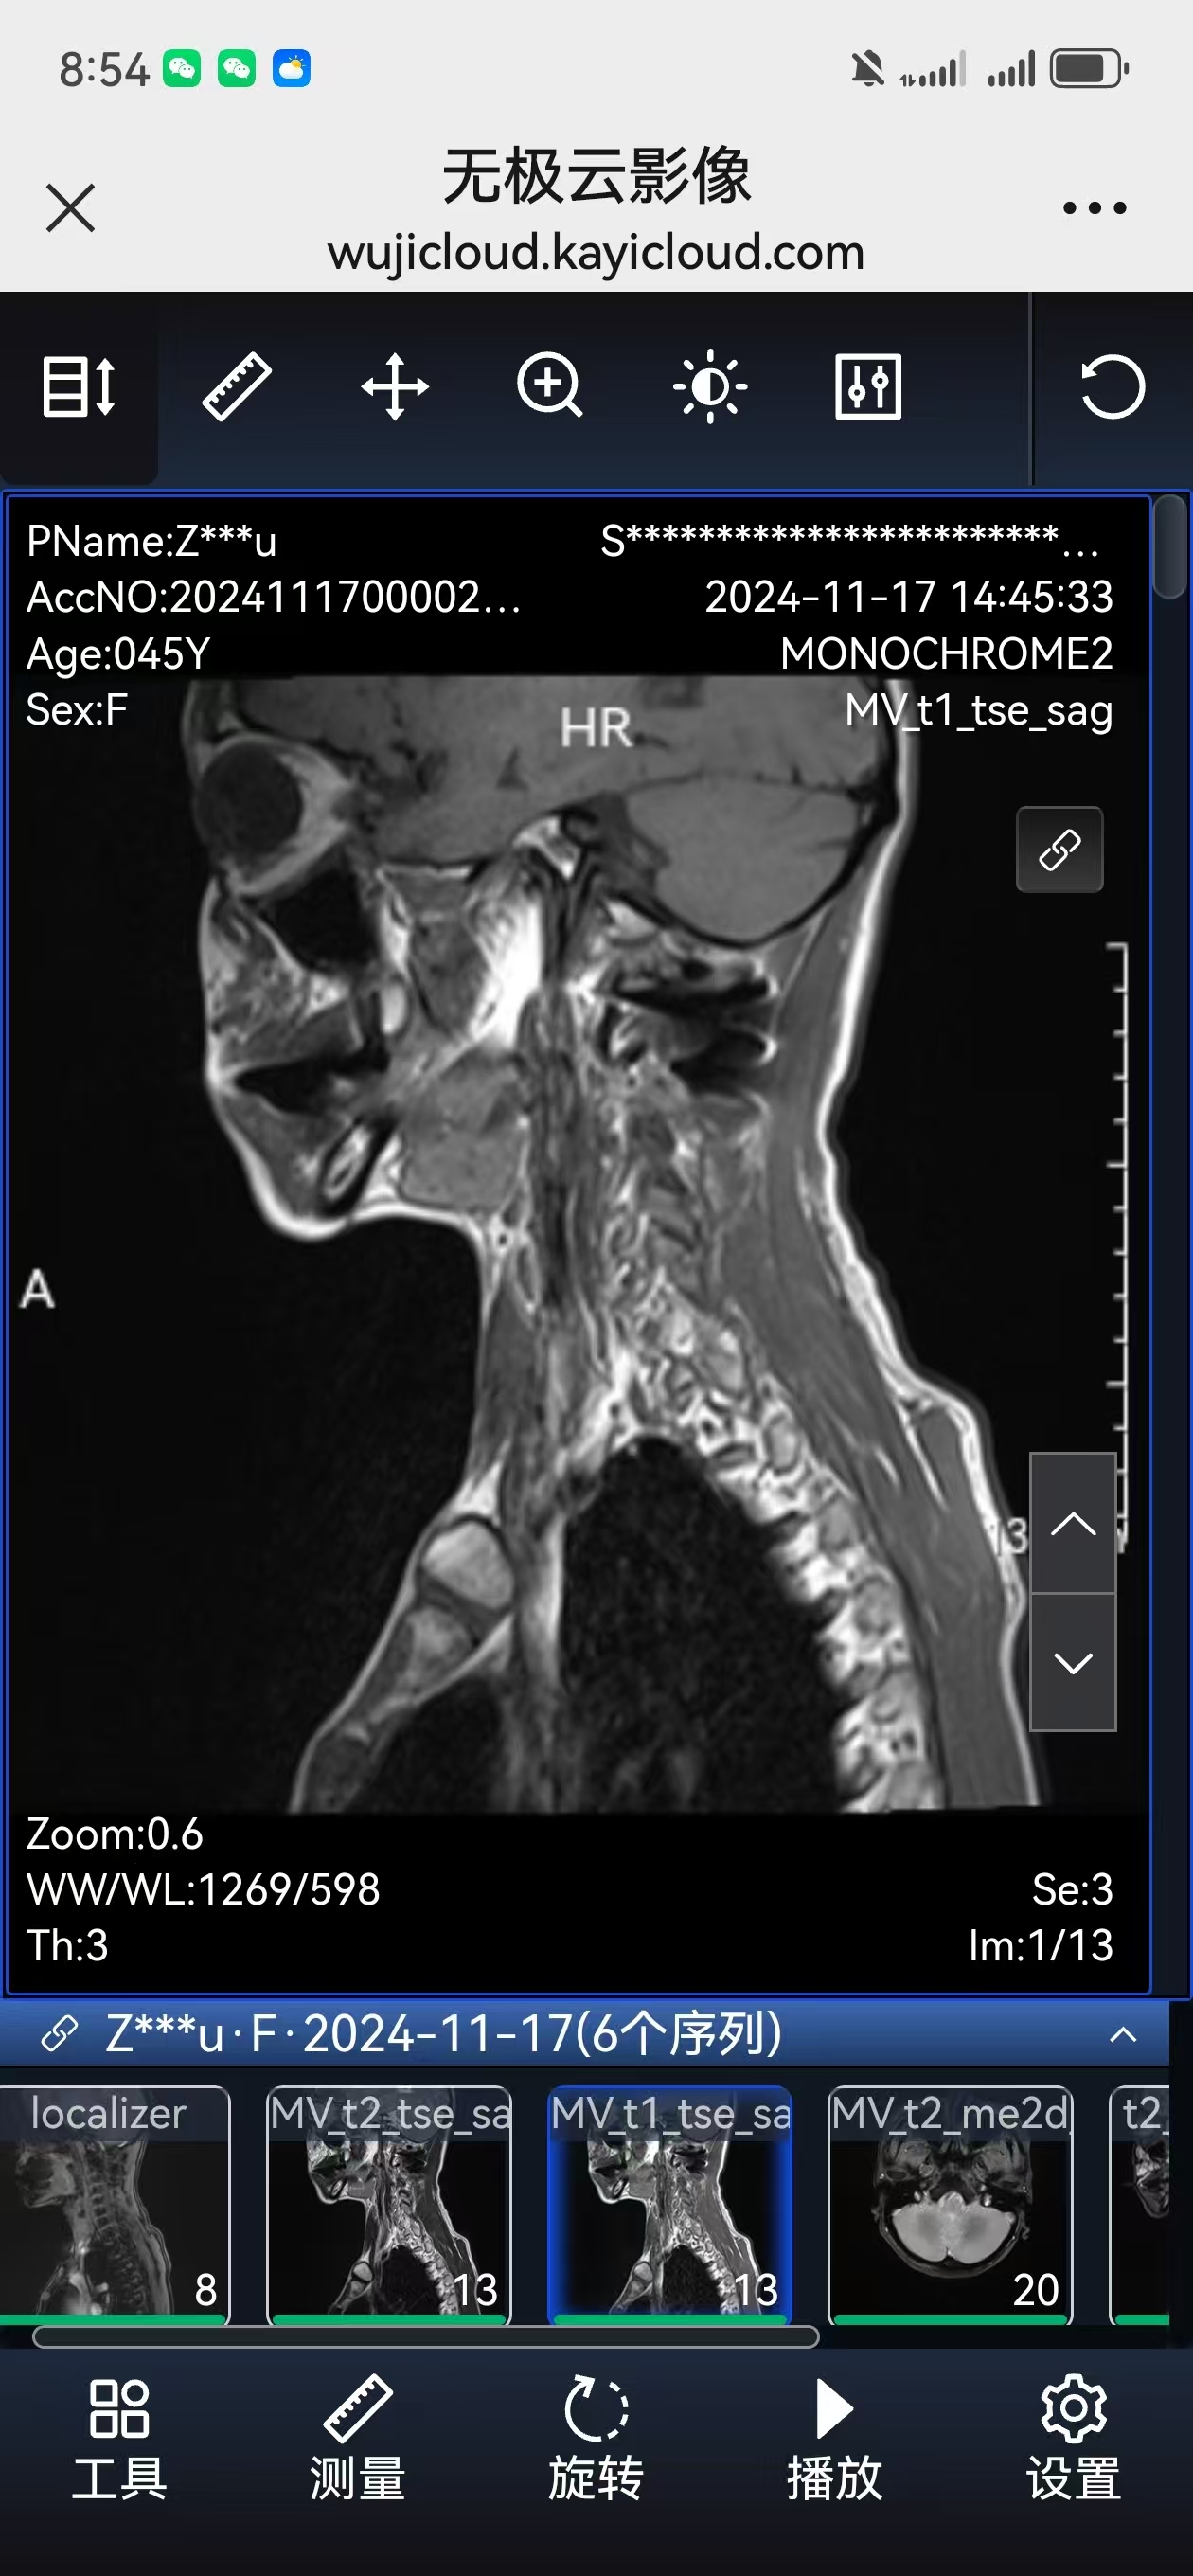

二次手术#

• 日期:2024.06.14

• 医院:北三医院

• 主刀:王超

• 术后状况:手脚无力的症状消失,低头时间久了脖子手术的地方酸痛。

• 术后影像:

• 2024.11.07,复查,对位良好。